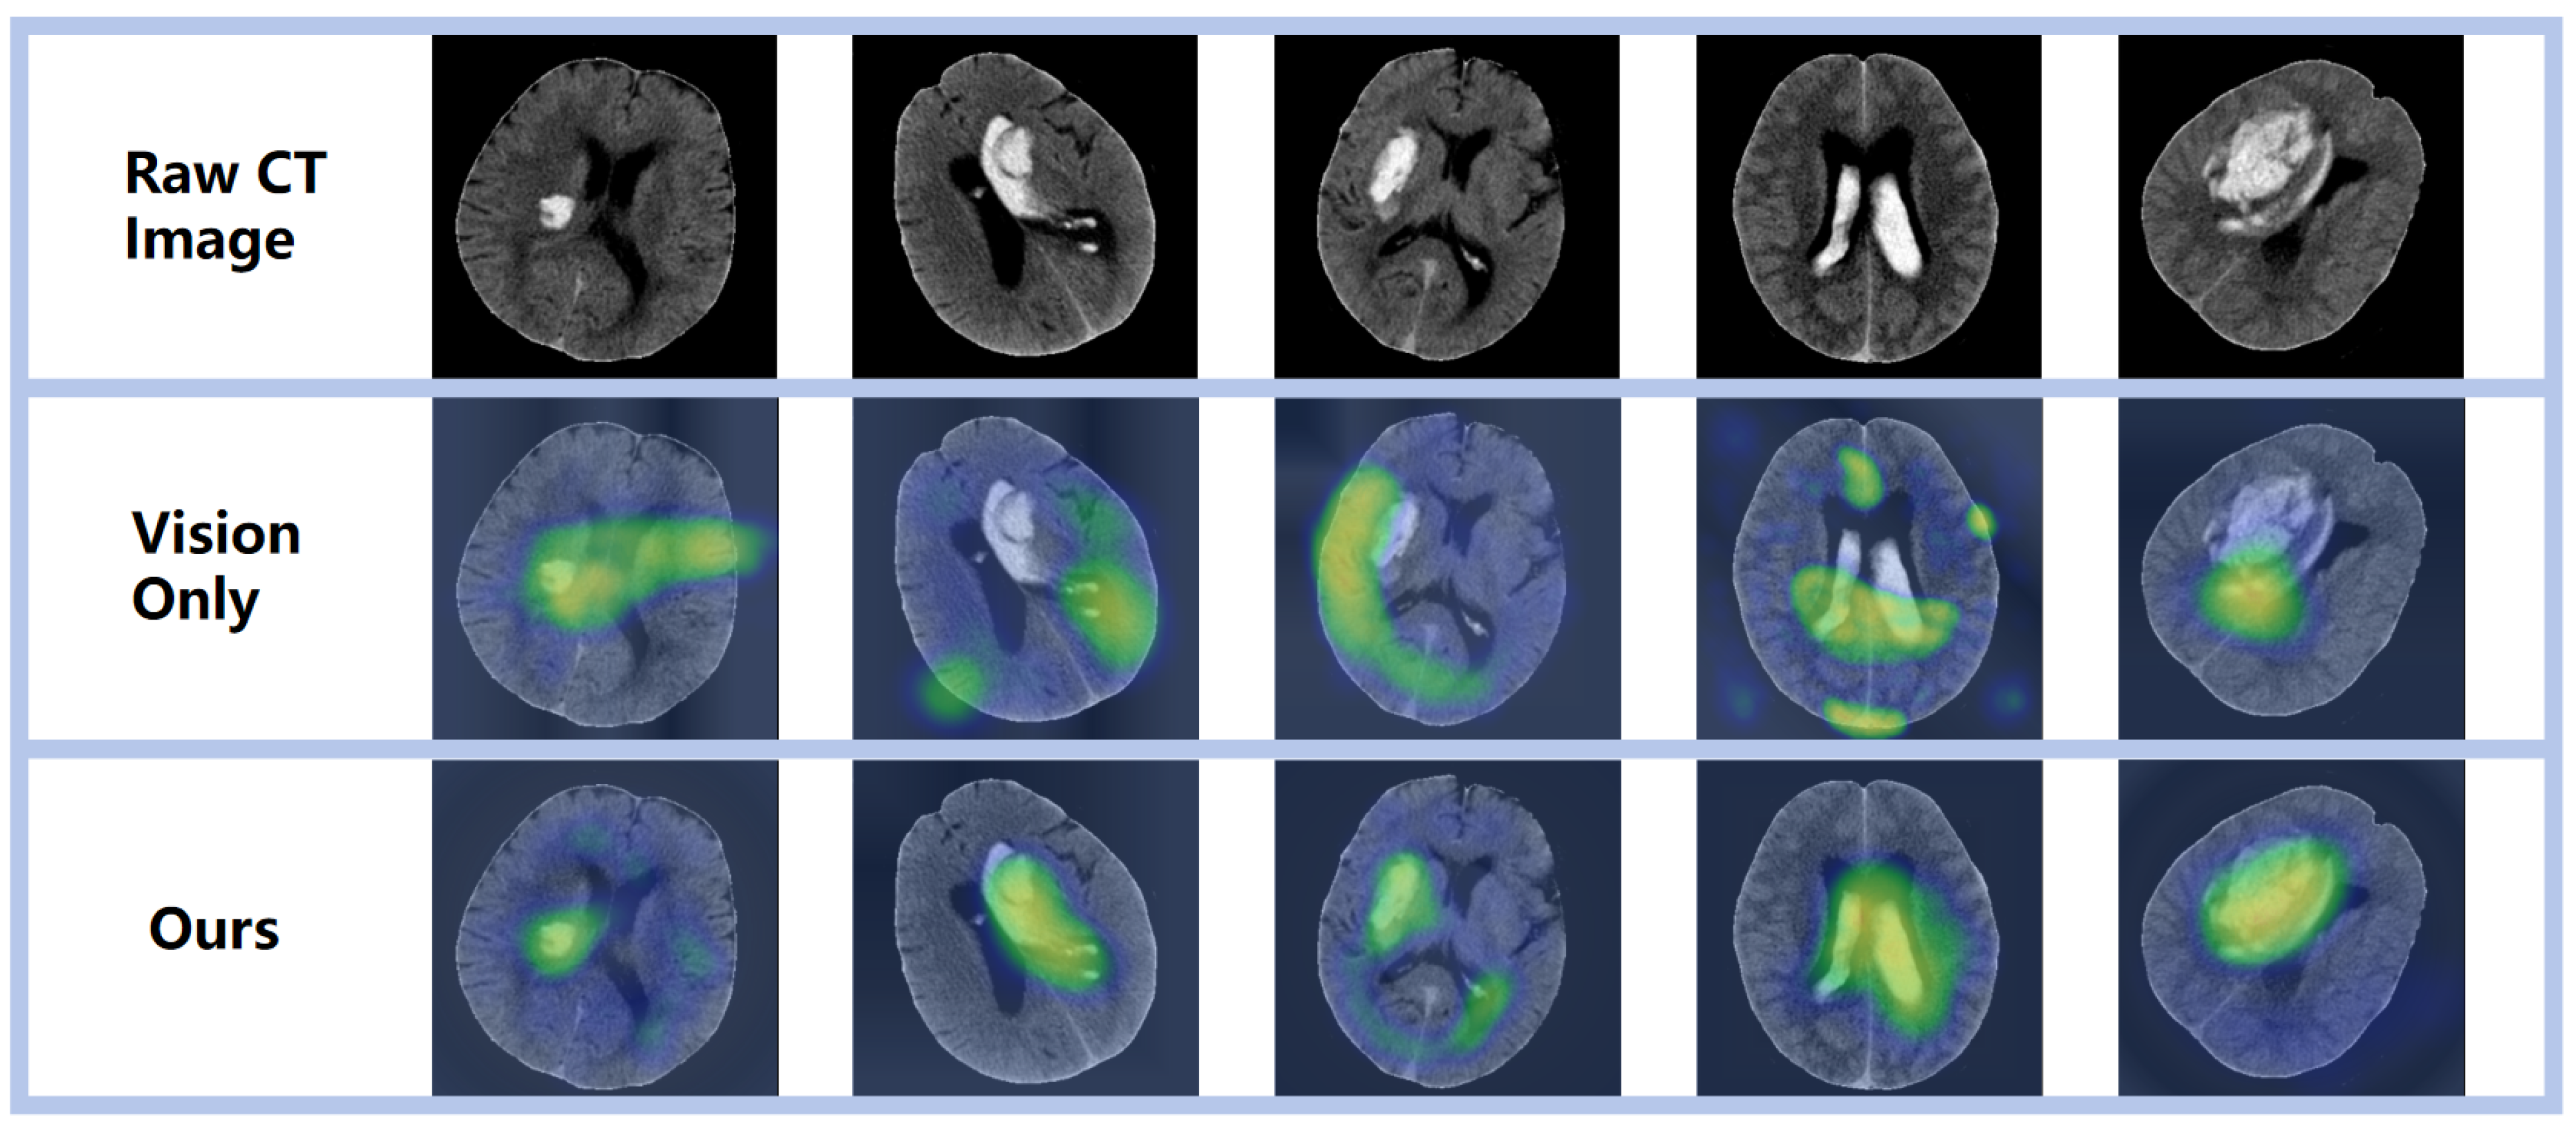

3.3. Visualization Analysis

Through meticulous examination of the images within the test set and the delineation of regions of interest, we gained a refined understanding of the network’s recognition accuracy of areas afflicted by ICH. As depicted in Figure 5, the employed visualization technique served a dual purpose: it corroborated the model’s remarkable precision in localizing hemorrhagic sites and underscored its capacity for accurate hemorrhage localization predictions—both of which are pivotal for assessing the network’s predictive capabilities. Moreover, these visualization outcomes provided a more profound insight into the network’s cognitive mechanisms, specifically its process for identifying hemorrhagic areas within images. Such clarity presents an opportunity to refine and enhance network performance. By deciphering the pivotal features and patterns that the network relies on for decision-making, we can implement targeted adjustments and advancements, thereby augmenting its efficacy in recognizing ICH. Consequently, this thorough inspection and visualization approach yielded indispensable insights for model refinement and the optimization of predictive performance. It equipped us with a deeper comprehension of the complexity inherent in the tasks at hand and propelled the enhancement of our models’ predictive acumen.

Figure 5. Visual representation of diverse prediction outcomes, emphasizing the activation zone of class association in the predicted network with a prominent red hue.